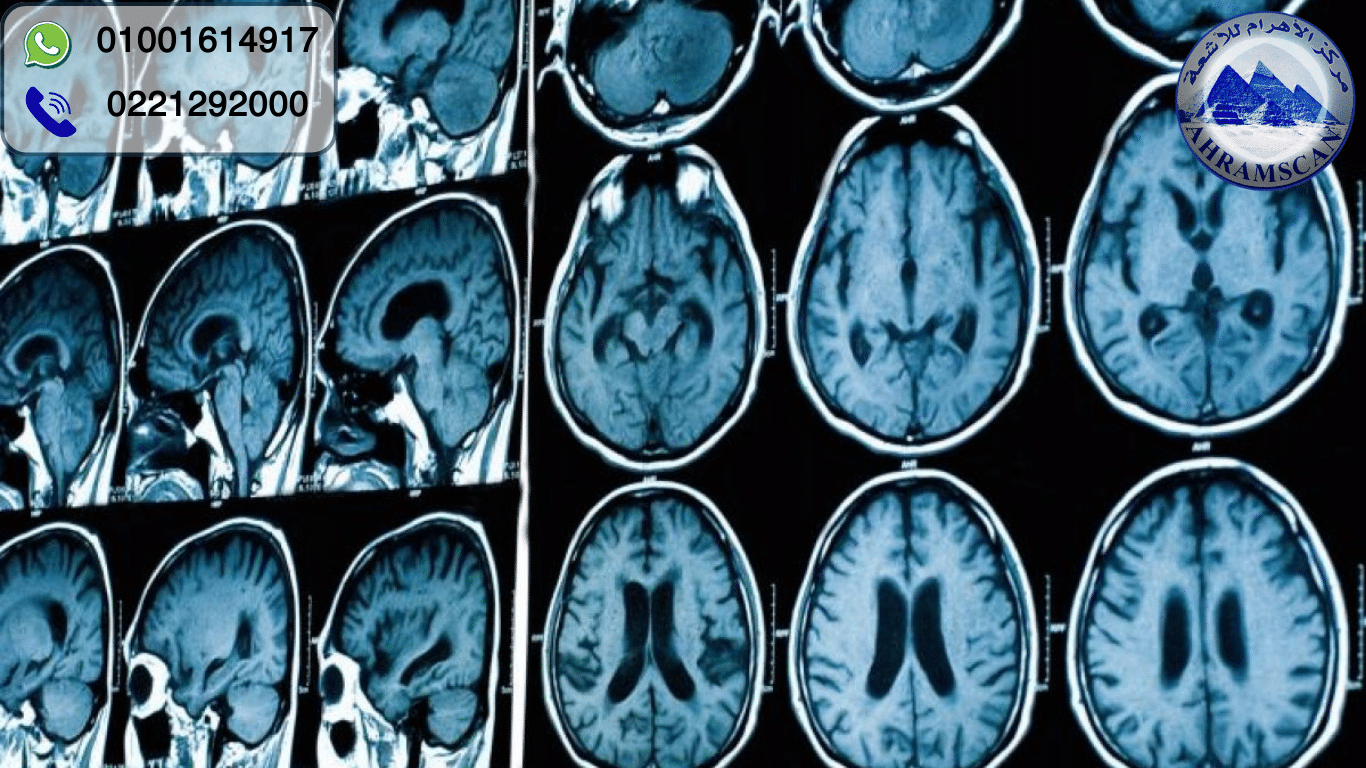

هل فكرت يومًا كيف يستطيع الأطباء رؤية ما يحدث داخل دماغك بدون جراحة؟ الأمر أشبه بامتلاك "كاميرا خارقة" تلتقط صورًا دقيقة لداخل الرأس. هنا يأتي دور أشعة مقطعية ع ...

الأشعة المقطعية للراس واحدة من أهم التقنيات التشخيصية التي يعتمد عليها الأطباء اليوم، ليس فقط لأنها تقدم صورة واضحة ودقيقة للدماغ، بل لأنها تمنح إجابات سريعة في ...

عندما يسمع أي شخص عبارة اشعة مقطعية على المخ، قد يشعر بالقلق أو الخوف، وهذا أمر طبيعي تمامًا، فالفحص متعلق بأهم عضو في الجسم الدماغ. وتُعد واحدة من أهم الفحوصات ...

أشعة رنين على المخ يعتمد عليها الأطباء للكشف عن أي مشكلة داخل الدماغ بدون تدخل جراحي وبدون التعرض للإشعاع. هذه التقنية تُستخدم اليوم في المستشفيات والمراكز الطب ...

يُعتبر إجراء فحص رنين مغناطيسي للمخ من أهم الفحوصات الطبية لتشخيص أمراض الجهاز العصبي. فبفضل قدرته العالية على إظهار التفاصيل الدقيقة لأنسجة المخ، أصبح هذا الفح ...

قراءة أشعة الرنين المغناطيسي للمخ ليست مجرد خطوة طبية روتينية، بل هي نافذة تُظهر أدق تفاصيل الدماغ، وتكشف الكثير مما لا يمكن رؤيته في الأشعة العادية أو المقطعية ...

التصوير بالرنين المغناطيسي للدماغ يُعد من أهم التقنيات الطبية الحديثة التي ساعدت الأطباء على رؤية تفاصيل دقيقة داخل المخ والجهاز العصبي. على عكس الأشعة السينية ...